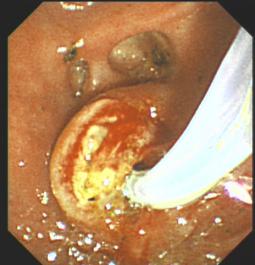

胆石症ERCP治疗